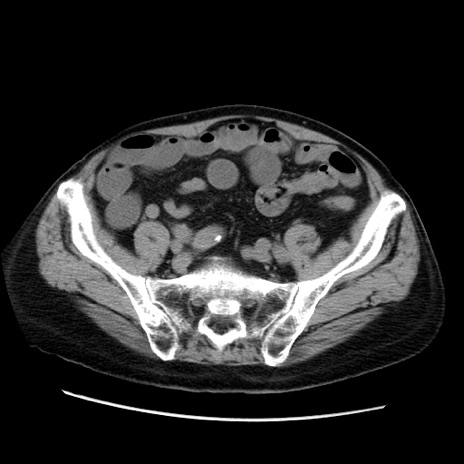

症例21(横断像)

【症例】70歳代男性

【現病歴】肝硬変・肝細胞癌にてかかりつけの方。約9時間前に食後より腹痛出現。症状が徐々に増悪し、嘔吐出現したため来院。

【既往歴】肝硬変、肝細胞癌(RFA、TACE後)